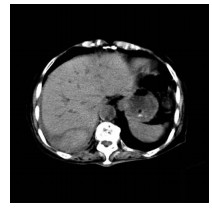

肝病超声诊断指南

中华医学会超声医学分会, 中国研究型医院学会肿瘤介入专业委员会, 国家卫生和健康委员会能力建设和继续教育中心超声医学专家委员会

2021, 37(8): 1770-1785. DOI: 10.3969/j.issn.1001-5256.2021.08.007

摘要(3138) HTML (6640) PDF (9311KB)(810)

超声检查无创、实时、价廉,无辐射、便于反复进行,是最常用的肝脏影像学检查方法。近年来,超声检查新技术如超声造影、弹性成像发展迅速,可有效鉴别肝内占位性病变性质、评估肝纤维化和门静脉高压程度以及监测肝病治疗效果,在临床肝病及其介入治疗中发挥重要诊断价值。本指南规范了肝病多模态超声技术(灰阶超声、彩色多普勒超声、超声造影、弹性超声)检查的仪器调置、患者准备及医生检查方法;对肝脏弥漫性病变(炎性病变、纤维化、硬化)、多种占位性病变及肝病介入操作的多模态超声技术诊断标准进行了定义和规范,同时推荐了超声监测周期及肝脏疾病超声诊断报告书写规范。